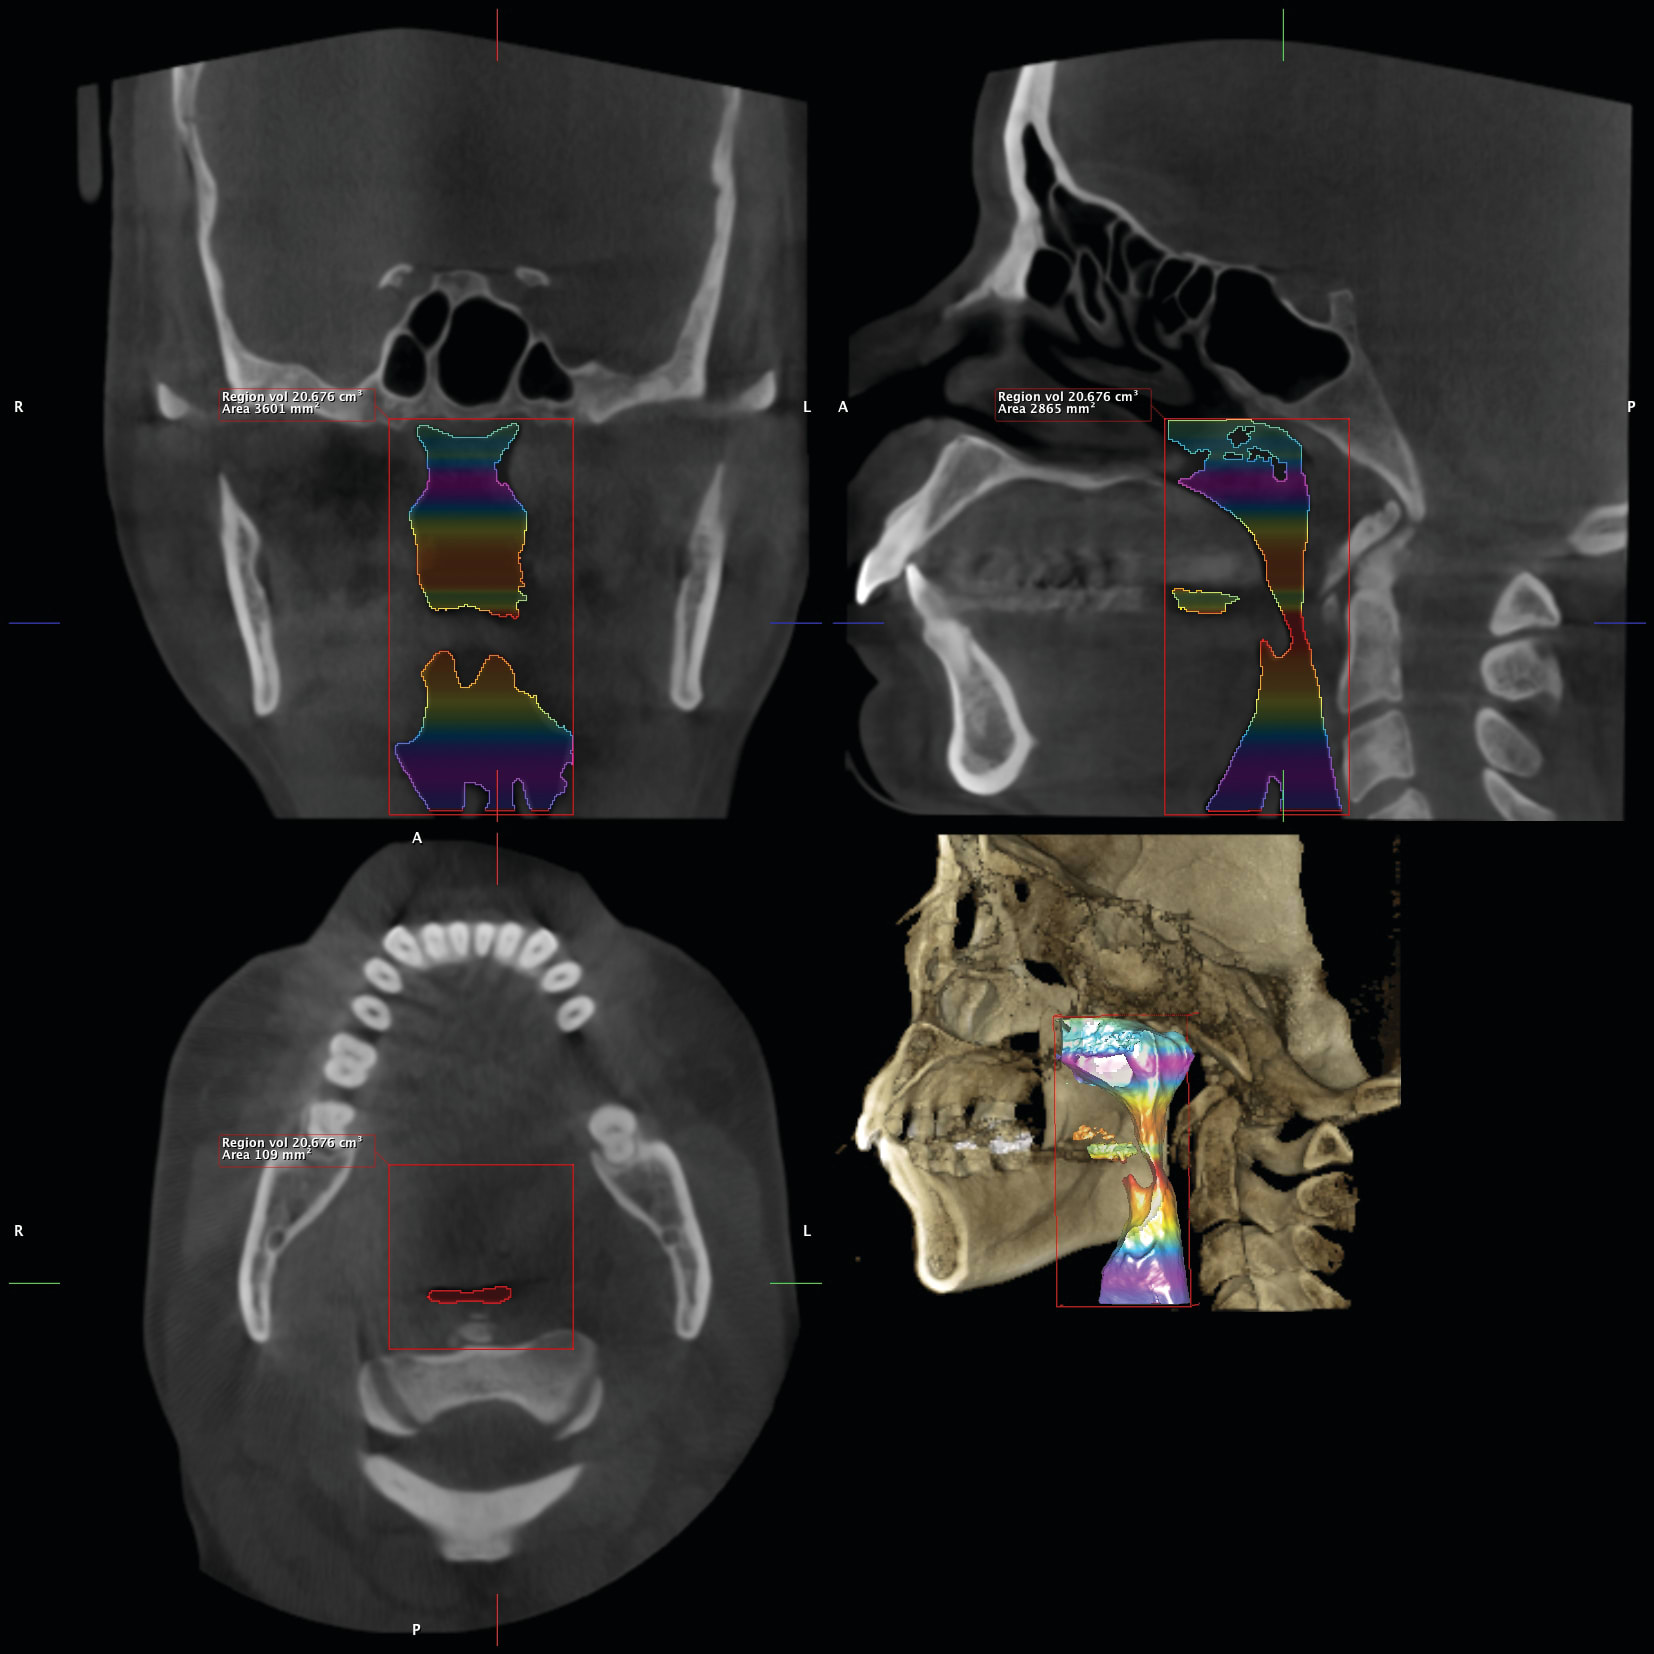

7. Any patient suspected of having an compromised airway. Granted, this is not known until the patient is scanned. However, if there is an inadequate airway, the location of the constriction could determine the type of treatment the patient receives. It could change the treatment plan from a camouflaged treatment to a mandibular advancement for example. A traditional ceph is not adequate in determining the size of an airway. The subject of imaging and treating compromised airway patients is experiencing more advancement in dentistry than any other subject. It is this clinician’s opinion that the orthodontic specialist should be the most qualified clinician to aid in the treatment of these types of patients. These patients deserve a multidisciplinary approach, perhaps more than any other type of patient we see in our practices. DICOM images are vitally important for the proper diagnosis and treatment of these individuals. Figure 28 and Figure 29 illustrate an example of this type of patient that had a chief complaint of overjet. She could be treated with the retraction of the upper anteriors. After further imaging, it was decided that a mandibular advancement would best serve her. Also note the osteophyte on C1 that is constricting the airway. This is not a common occurrence. This osteophyte needs to be removed. So the DICOM images changed our treatment plan. Figure 30 illustrates another patient seeking treatment after surgical relapse. This patient will need to be treated with surgery again. Note the restricted airway at the hypo pharynx. This must be treated prior to the re-treatment of this case. Also note the upper centrals have been torque through the lingual cortical bone. These two problems are not viewed with conventional 2D images.